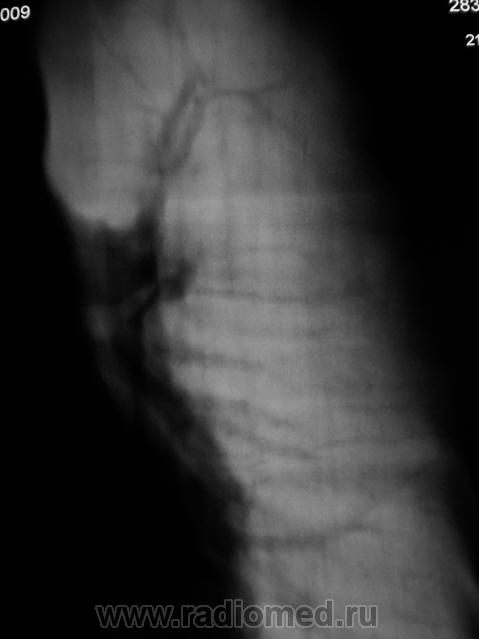

Пациент, подросток направлен из детского отделения на рентгенографию грудной полости с диагнозом "Правостороняя верхнедолевая пневмония". Как показал анализ рентгенограммы органов грудной полости в прямой стандартной проекции, исследование рентгенографией "по поводу пневмонии" не ограничилось.

Гипоплазия верхней доли левого лёгкого. Гипоплазия левой легочной артерии или её ветвей.

Явная аномалия развития ветвей левой лёгочой артерии. На основании каких признаков, вы думаете о гипоплазии верхней доли левого лёгкого?